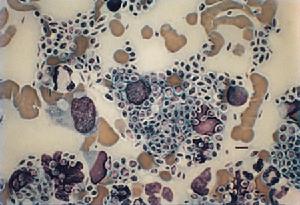

孢子絲菌病主要侵犯皮膚、黏膜、局部淋巴系統,引起肉芽腫性損害。肺內病變初期為段性分布的支氣管炎和支氣管肺炎。病理變化為非特異性炎症改變,浸潤的炎症細胞包括中性粒細胞、淋巴細胞、漿細胞及少量類上皮細胞。隨病程遷延,形成慢性非特異性肉芽腫,導致結節性肺炎,典型病變由內向外依次為:中央區為慢性化膿區,主要由中性多核白細胞所組成的小膿瘍,並混有少數組織細胞和淋巴細胞;周圍有大量上皮細胞和多核巨細胞;外圍主要為淋巴細胞和成纖維細胞。活檢組織切片先以澱粉酶在37℃處理1h後作PAS染色,可見4~6μm大小的圓形或卵圓形小體,有時尚可見4~8μm長的雪茄菸形小體及星狀小體。

(1)直接鏡檢:取痰液、膿液或活檢組織直接塗片,作革蘭染色或PAS染色,在多核細胞內或大單核細胞內或細胞周圍,可見有革蘭染色陽性、圓形或梭形,直徑2~5μm小孢子。偶見菌絲及星形體。